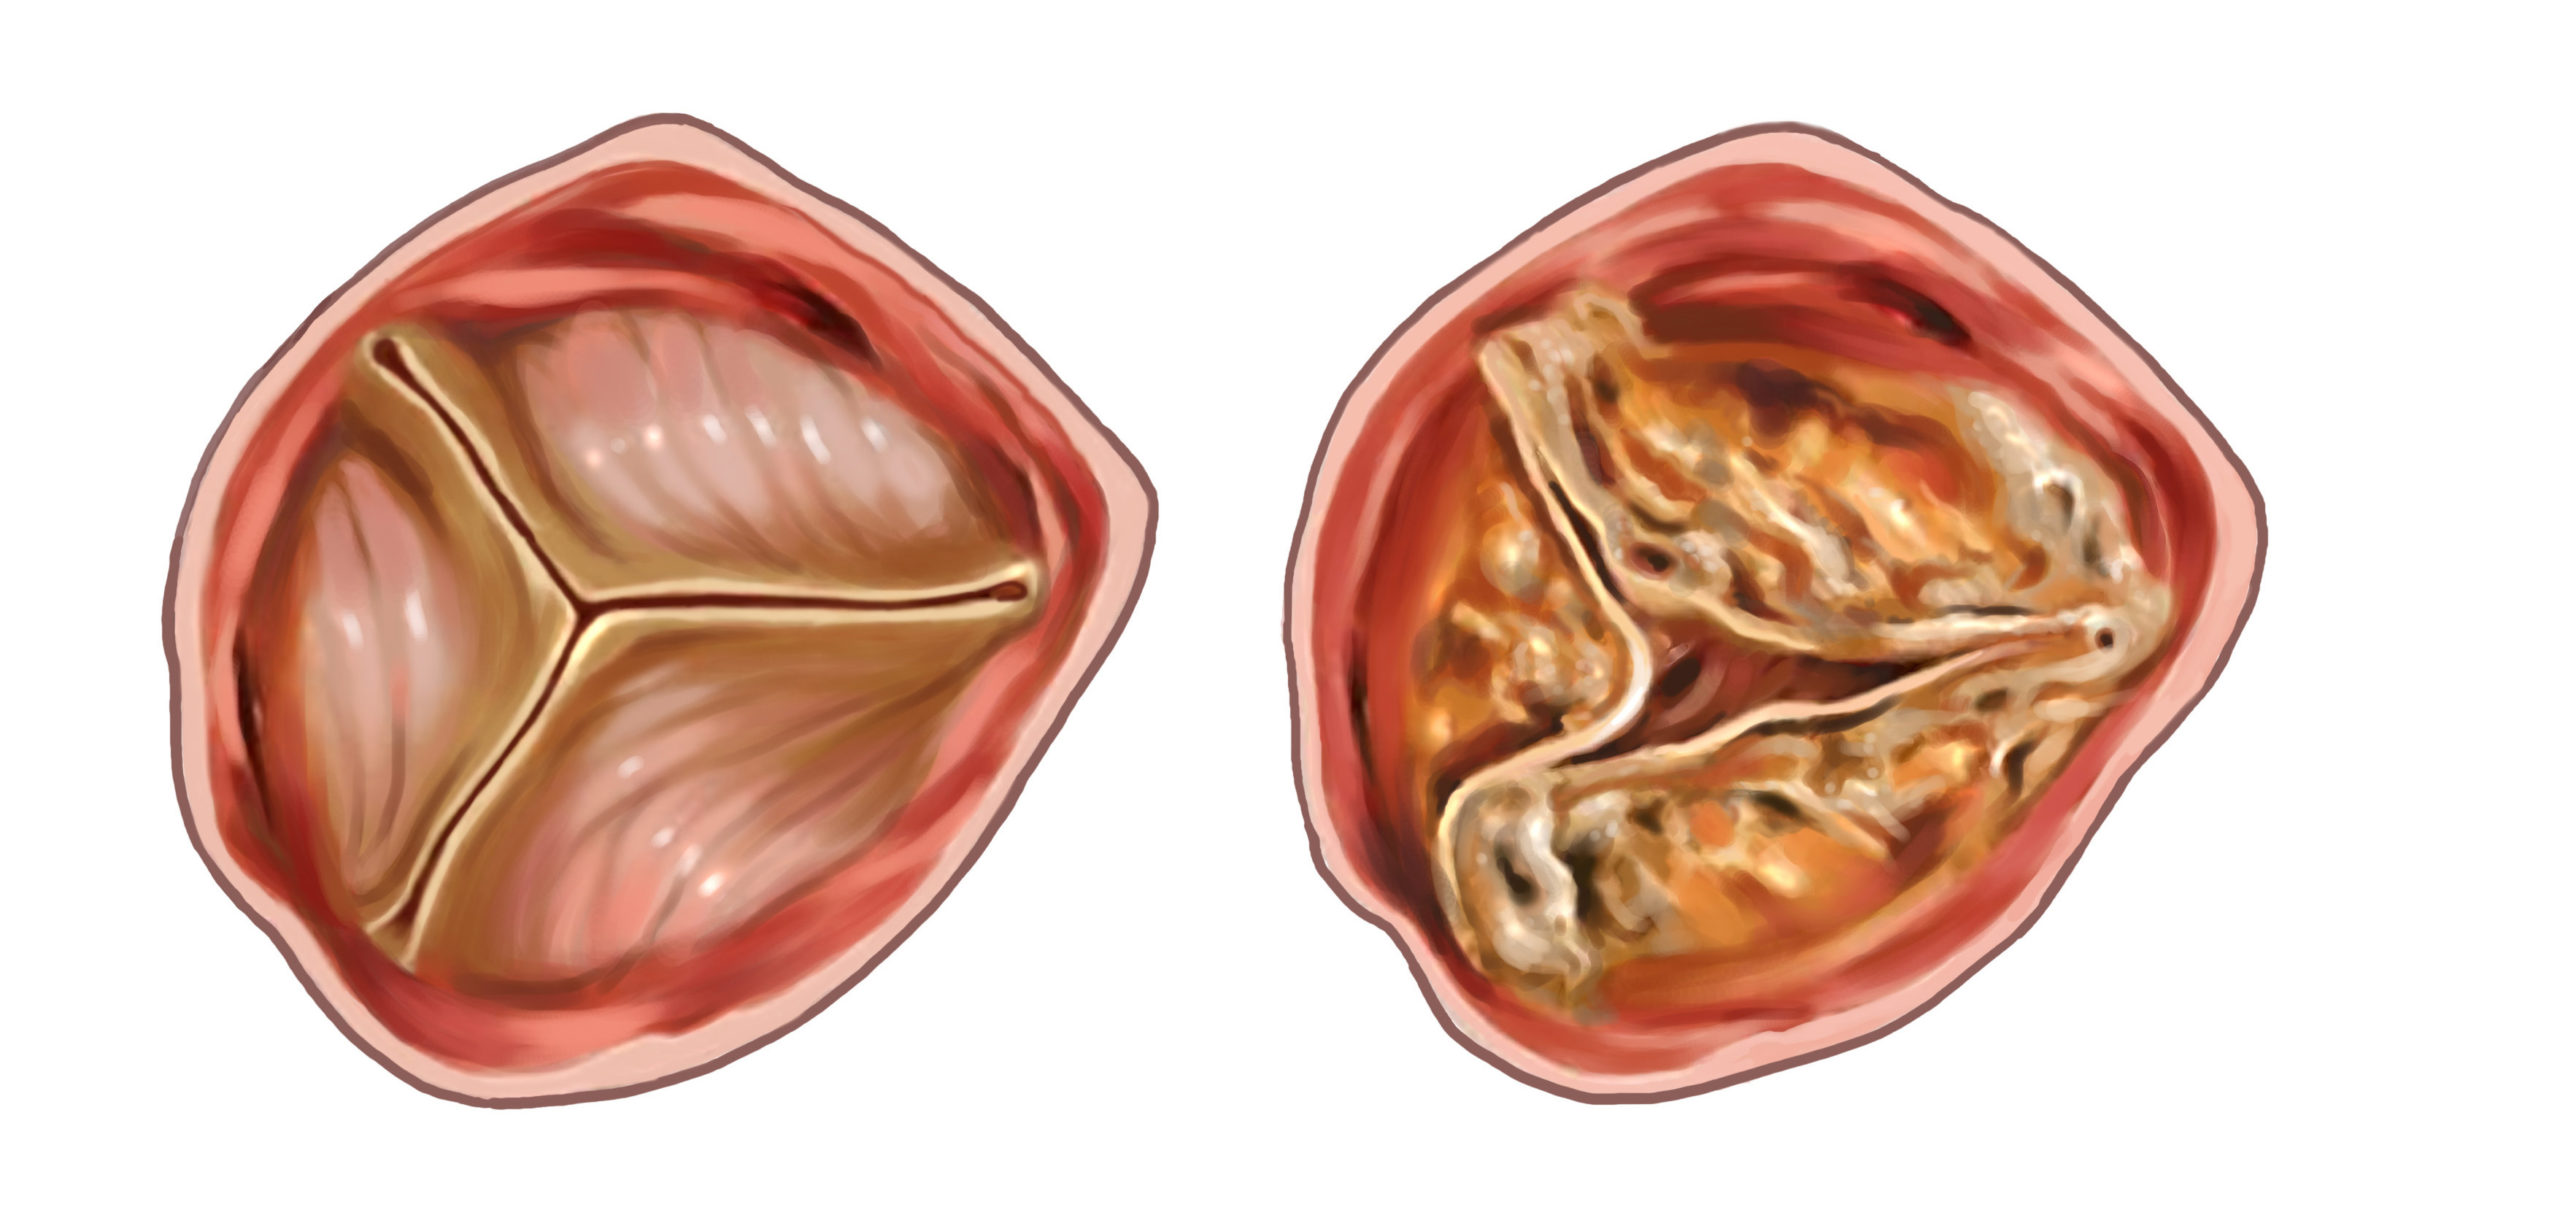

Фотографии и информация о приобретенных пороках сердца